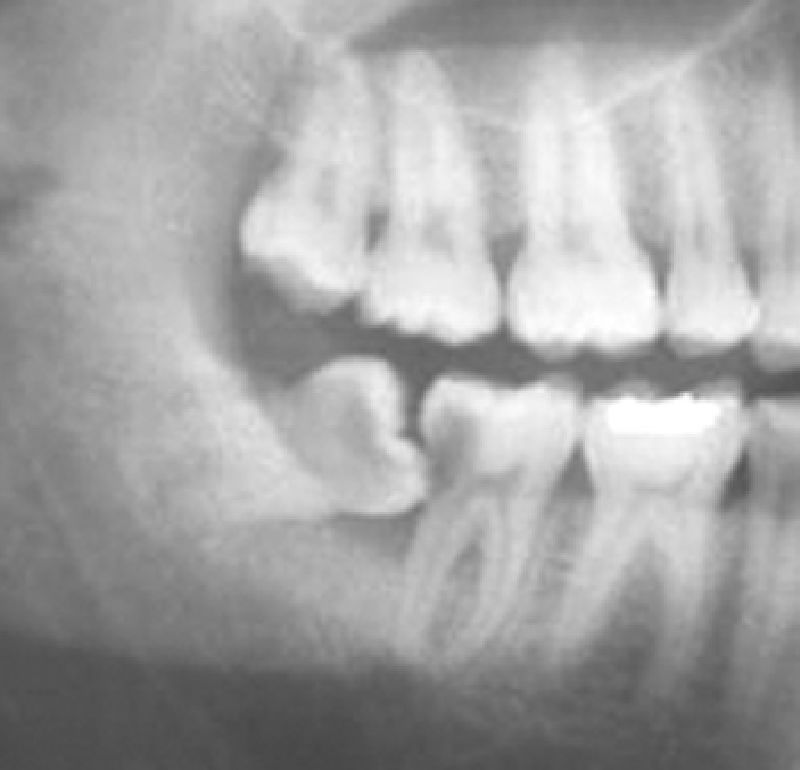

Wisdom teeth or Third molars are the last teeth in the jaw, normally stuck in jaw bone behind all the teeth. Inadvertly, their location is also tricky with their roots being very close to important nerves and blood vessels running in the jaws.

With evolution, the size of the human jaw has decreased. So wisdom teeth do not get adequate space to come out straight, and end up putting pressure on the front tooth (2nd molar) while erupting. This is why most 18 to 22 year olds face pain during wisdom teeth eruption.

Sometimes, if tooth size and jaw size match, the third molar erupts without pain, but it may erupt tilted- which can cause 2 problems. It can lead to gum impingement in that area, or it can cause a naturally-uncleanable site leading to decay of the 2nd or 3rd molar.